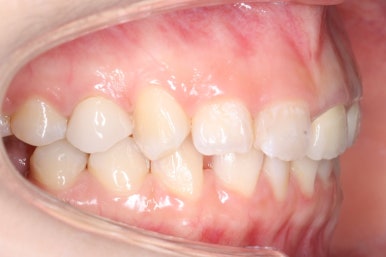

측면에서 본 모습입니다.

자리가 점점 넓어지는 것이 보입니다.